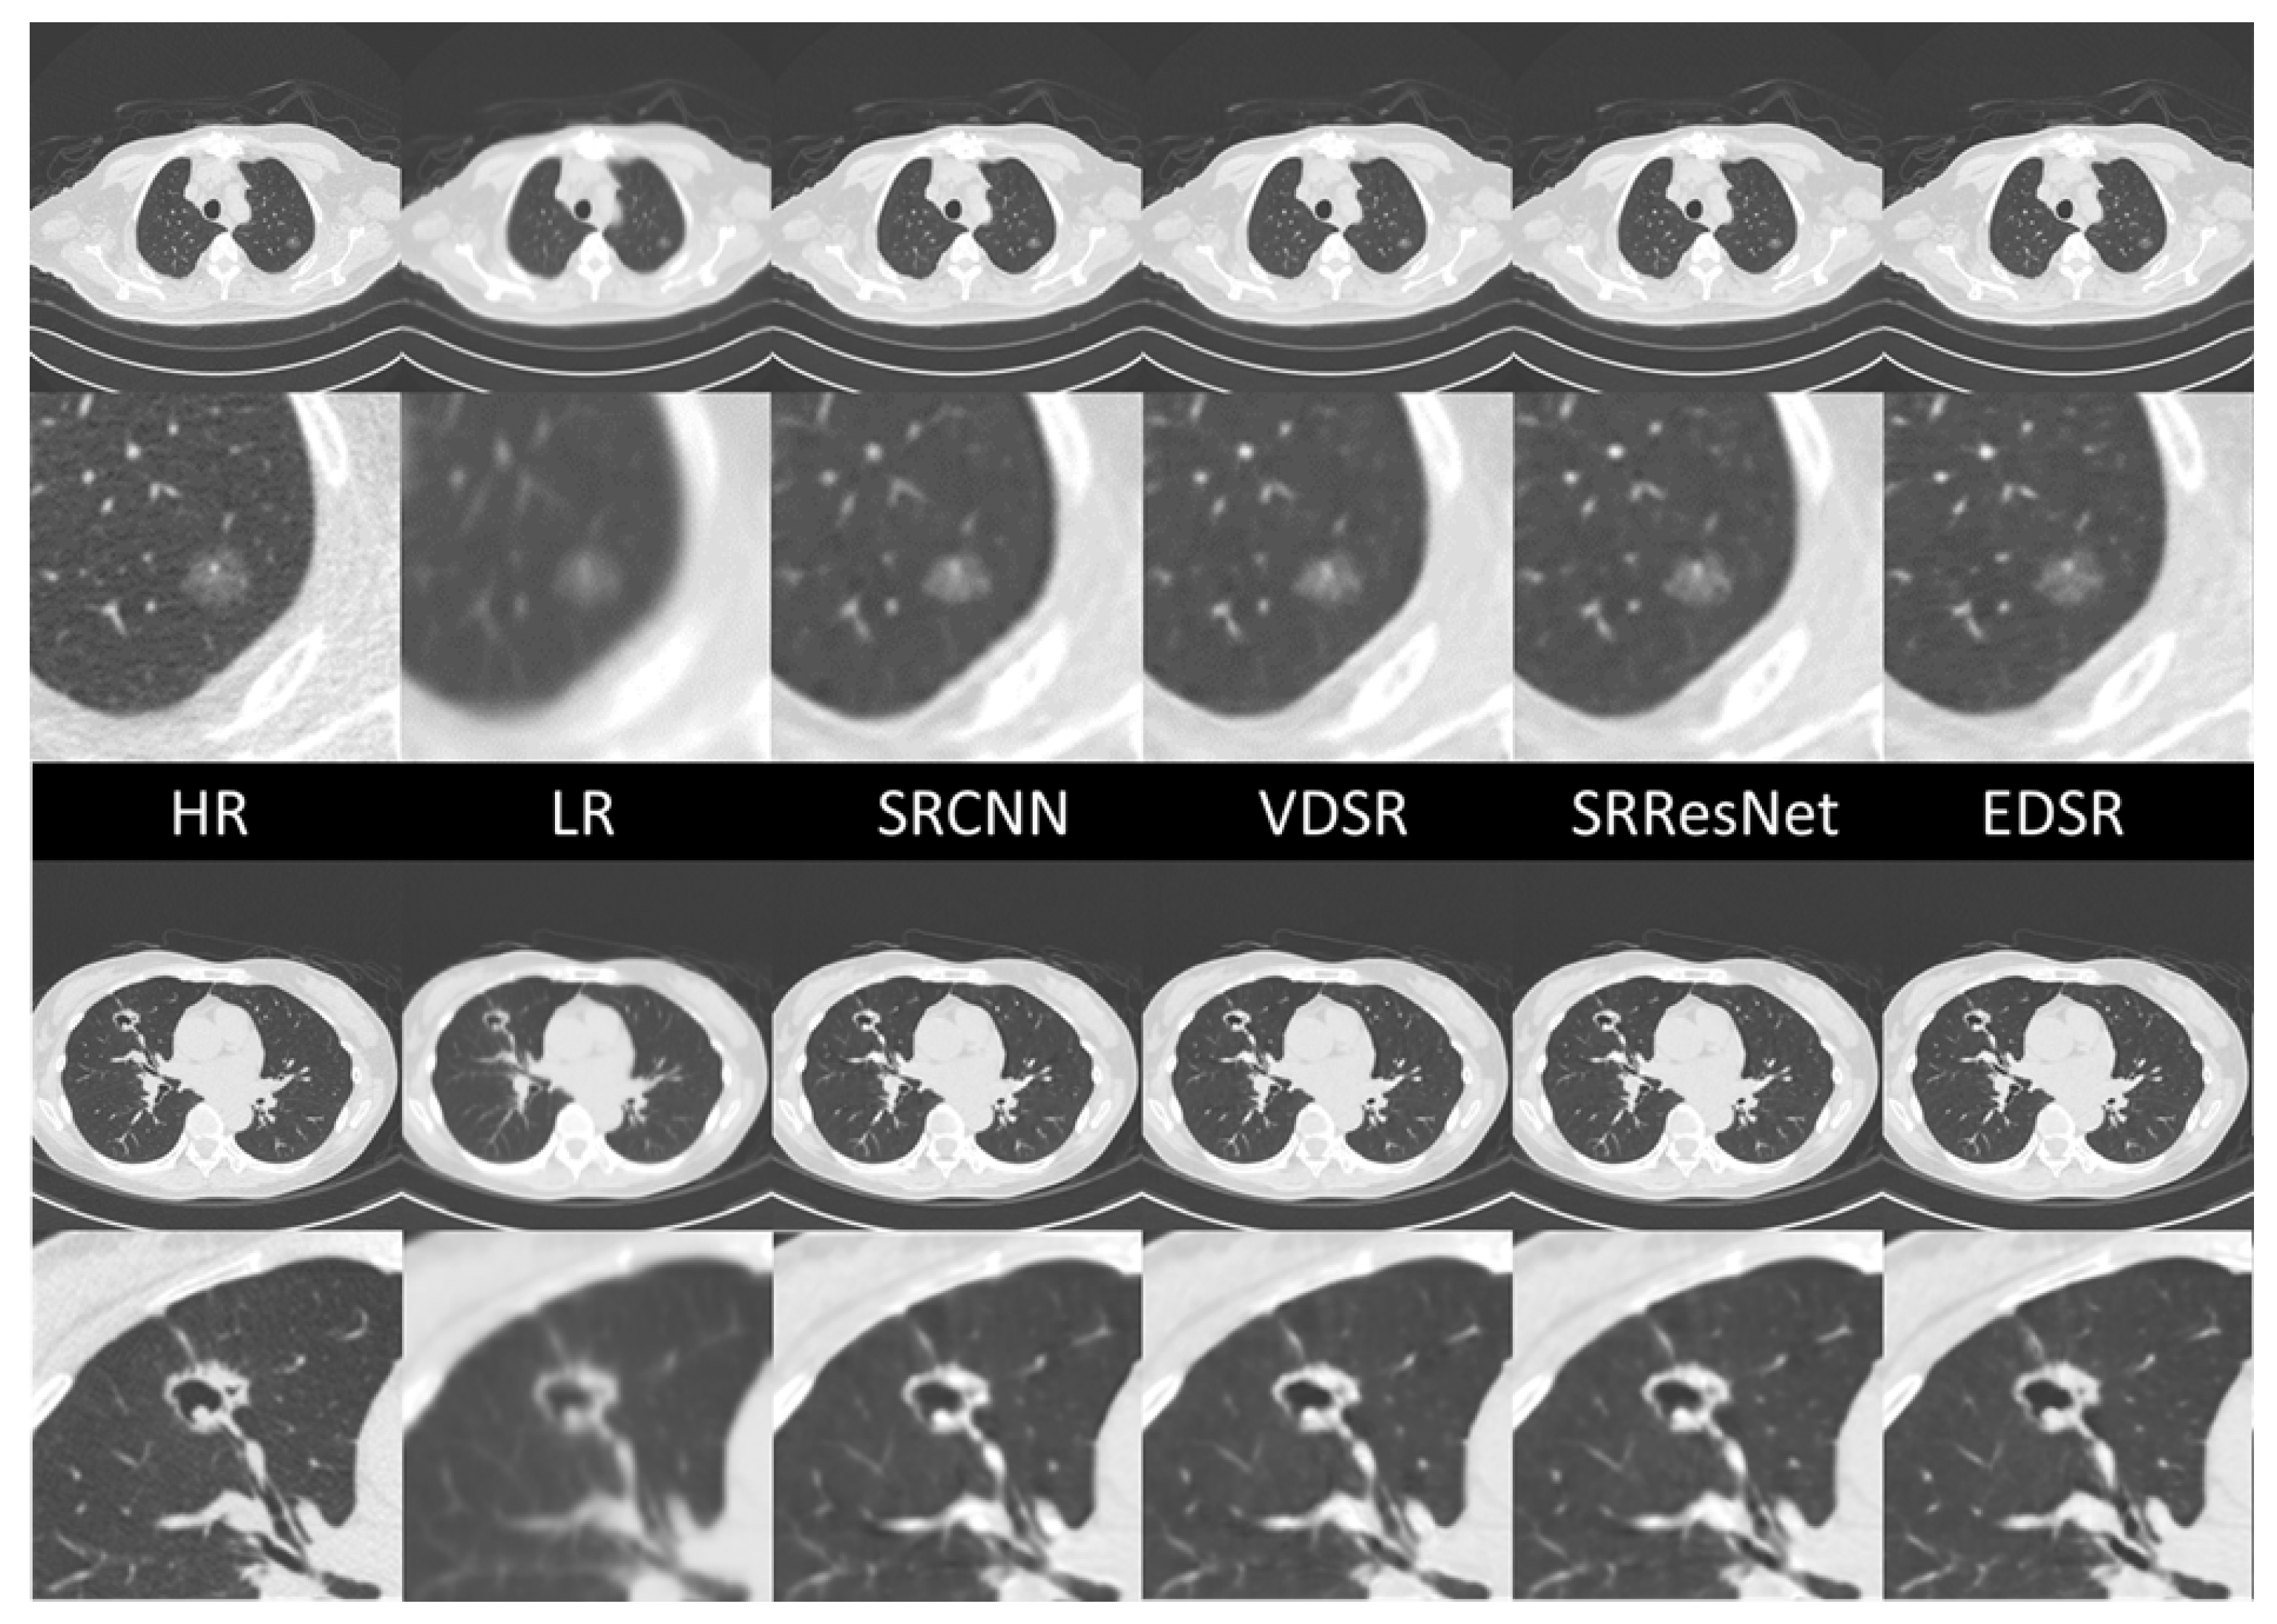

The ground-truth HR images, LR images, and sample comparisons for each SR DICOM slice generated along the sagittal axis are presented in Figure 9. The upper case is typical ground glass nodule that was confirmed to be early-stage lung cancer through surgical resection. All SR images maintain the ground glass features of this lesion, but only EDSR maintains the correct size and structure in terms of human visual quality. In the EDSR images, the fine structures of the surrounding lung markers are more clearly defined and correctly connected. The lower case is a cavitary lesion. Although the details of the upper border of the cavitary lesion are blurred in all SR images, the EDSR image preserves the arrangement of the proximal vessels and bronchi.

Figure 9. SR image samples of different AI models. All images were generated by applying SR models in the sagittal plan.